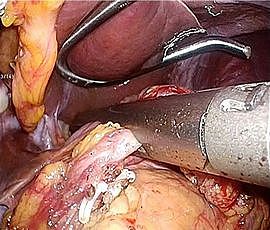

[胃がん] 手術:腹腔鏡下胃全摘術

手術画像